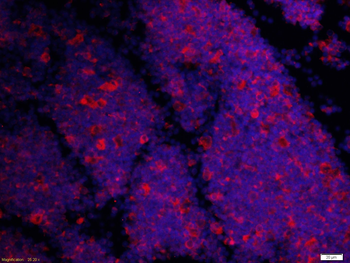

50 μl, 100 μl, 200 μlAnti-Aurora A/AURKA Antibody [orb1290027]

ELISA, FC, IHC, WB

Human

Rabbit

Polyclonal

Unconjugated

10 μg, 100 μgChemerin Rabbit Polyclonal Antibody [orb156351]